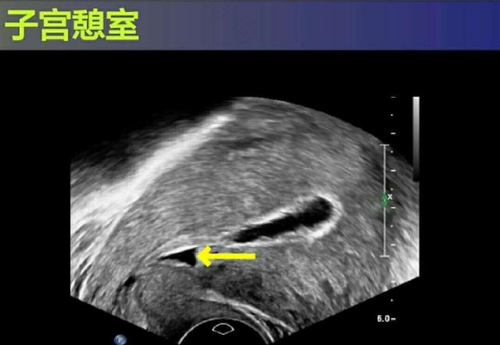

说到子宫憩室,很多人不明白这是什么,其实这是一种比较常见的手术并发症,在我国发病率很高,这是由于在手术过程中出现了一些问题导致的,其中子宫手术恢复不良是主要原因。那么,子宫憩室有哪些危害呢?

其次,子宫切口憩室是剖腹产后容易发生的一种症状,它是由于伤口愈合不良引起的子宫肌肉缺损,这也是剖腹产的并发症,容易引起子宫不规则的出血,所以如果想要再次怀孕,很容易导致子宫切口破裂。值得注意的是,要想再次怀孕,要进行手术修补,只有愈合后才可以怀孕。